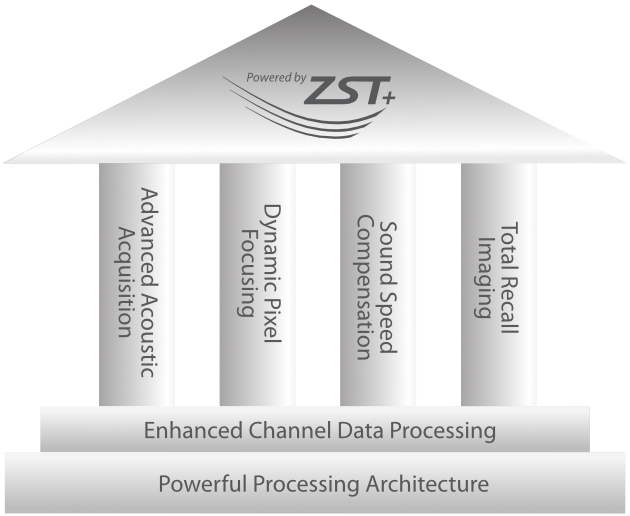

Con tecnologia ZST+

La piattaforma ZST+ rappresenta uno straordinario balzo in avanti nella tecnologia degli ultrasuoni, passando dal beamforming convenzionale all'elaborazione dei dati di canale. Questa innovazione rivoluzionaria supera i tradizionali compromessi tra risoluzione spaziale, risoluzione temporale e uniformit├Ā dei tessuti, dando vita a una qualit├Ā d'immagine senza pari che consente infinite soluzioni di imaging.